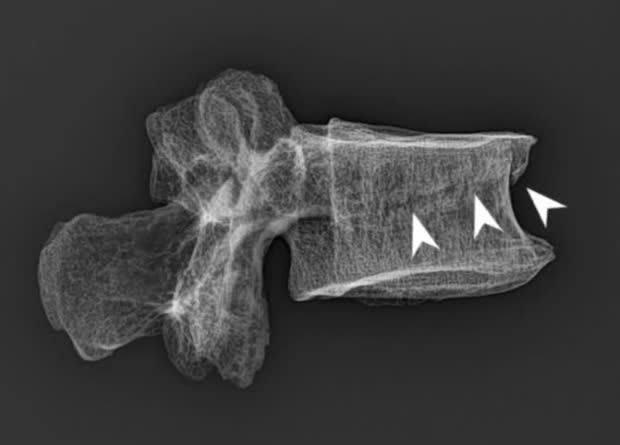

Сегодня одним из самых распространенных черепно-лицевых пороков развития выступают орофациальные расщелины, которые встречаются примерно 1,4 раза на тысячу новорожденных. Медики выделяют три основные формы этого врожденного порока: расщелина верхней губы (хейлосхиз), губы и неба (хейлогнатопалатосхиз) или только неба (палатосхиз). В разговорной речи для описания таких патологий используют понятия заячья губа и волчья пасть. В патогенезе этого заболевания участвуют как генетические, так и экологические факторы.

Хотя в настоящее время орофациальные расщелины встречаются достаточно часто, в археологическом контексте останки людей с такими пороками развития редки. Самое известное исключение — это фараон Тутанхамон, гробницу которого обнаружили в «Долине Царей» в 1922 году. Помимо волчьей пасти, палеопатологи диагностировали у него косолапость, болезнь Келера и некоторые другие заболевания и травмы. В общей сложности археологам известно около 50 подобных примеров, причем в 80 процентах случаев орофациальные расщелины обнаружены у взрослых людей. Так, останки одного из индивидов были найдены на Алтае, во время раскопок погребения андроновской (федоровской) культуры в могильнике Фирсово-XIV. Он был молодым мужчиной 18–23 лет, который умер около 1883–1665 годов до нашей эры.